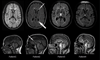

Figures